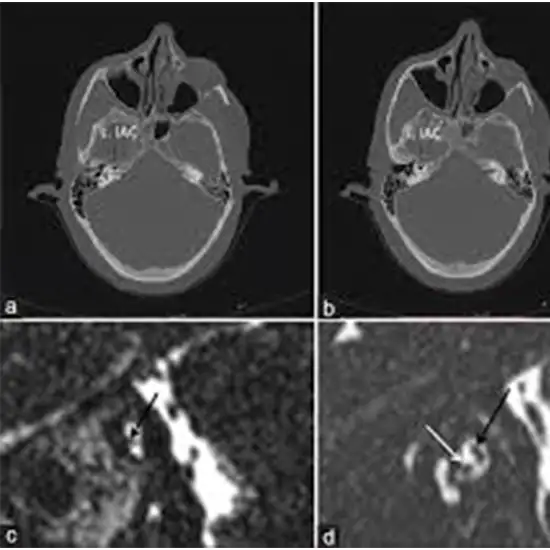

A computed tomography scan (CT or CAT) of the internal auditory canal, also known as cross-sectional imaging, uses a rotating X-ray beam to examine different levels, or slices, of the skull bones leading from the ear. The radiologist can assess skull bones for injury, infection, fluid levels, and abnormalities by looking at these slices.